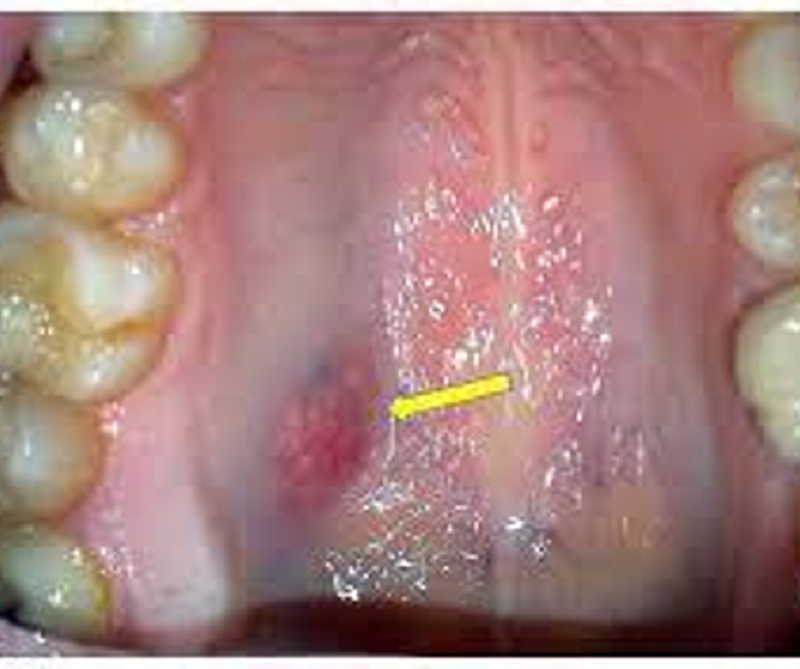

{"name":"Oral Path ID Chapter 6-9", "url":"https://www.quiz-maker.com/QPREVIEW","txt":"This condition is linked with Keratinosis of the palms of the hands & the soles of the feet. Individuals with this condition are likely to experience tooth mobility and premature tooth loss., This Term is used to describe The Appearance of type III (hypomaturation) Amelogenesis Imperfecta, Radiographs of a person with this condition appear to have a multilocular or “soap bubble” appearance","img":"https://www.quiz-maker.com/3012/CDN/92-4508546/final-pic-1.png?sz=1200"}